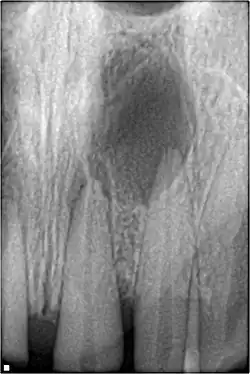

Pulpal necrosis

Pulp necrosis usually occurs either as ischaemic necrosis (infarction) caused by disruption to the blood supply at the apical foramen or as an infection-related liquefactive necrosis following dental trauma (2). Signs of pulpal necrosis include[42]

- Persistent grey colour to tooth that does not fade

- Radiographic signs of periapical inflammation

- Clinical signs of infection: tenderness, sinus, suppuration, swelling

Treatment options will be extraction for the primary tooth. For the permanent tooth, endodontic treatment can be considered.

Pulpal obliteration

4–24% of traumatized teeth will have some degrees of pulpal obliteration that is characterized by the loss of pulpal space radiographically and yellow discolouration of the clinical crown. No treatment is needed if it is asymptomatic. Treatment options will be extraction for symptomatic primary tooth. For symptomatic permanent tooth, root canal treatment is often challenging because the pulp chamber is filled with calcified material and the drop-off sensation of entering a pulp chamber will not occur.[44]